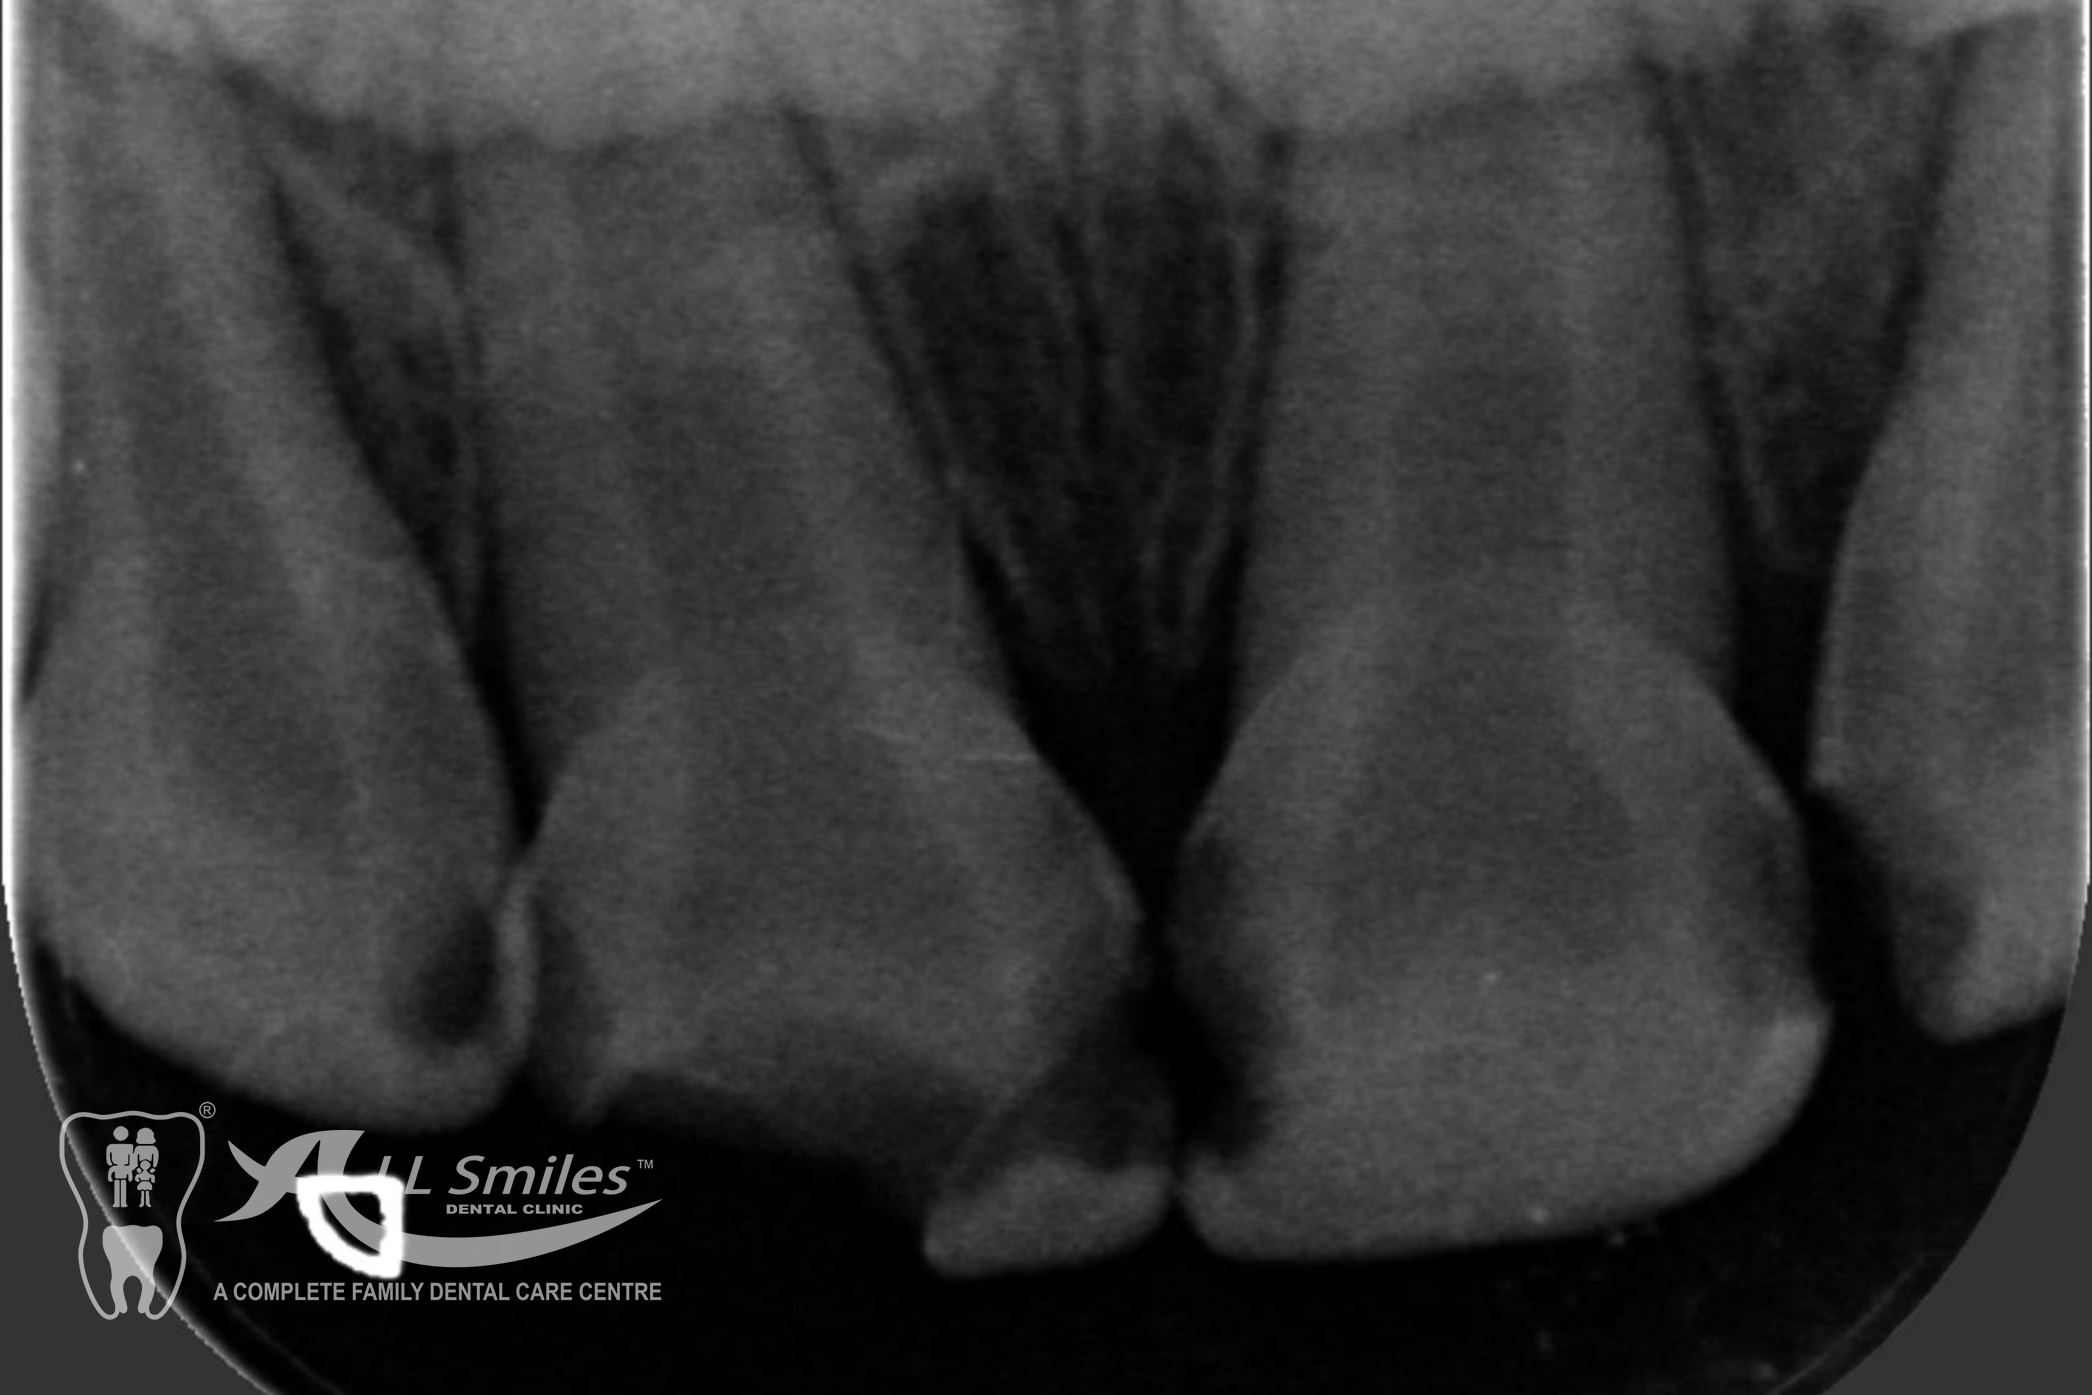

Root Canal Gallery